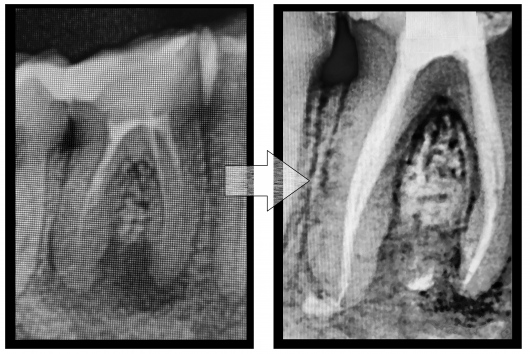

Jestem Amerykaninem, ale mieszkam w Polsce ponad 10 lat. Zajmuję się zachowawczą, leczeniem kanałowym pierwotnym i wtórnym pod mikroskopem, protetyką i prostą chirurgią. Wykonuję też Bonding i Flow Injection Technique.

Endodoncja mikroskopowa

Leczenie endodontyczne